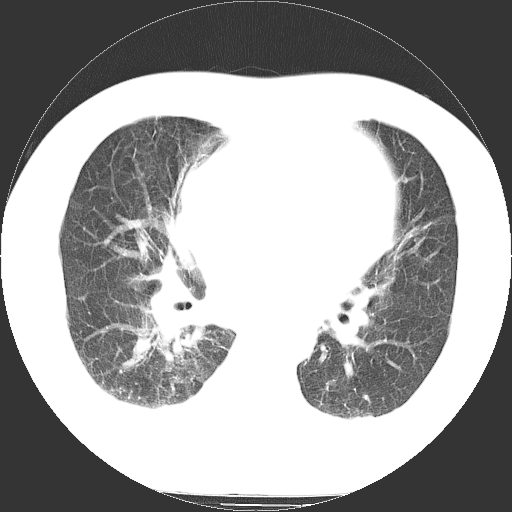

标题: CT21804:男,65岁,咳嗽、咳痰、发热5天。 [打印本页]

男,65岁,咳嗽、咳痰、发热5天。

慢支 肺间质纤维化合并感染!

支气管扩张合并感染,胸膜肥厚

考虑慢支并感染,肺间质纤维化。

两肺间质性炎症并感染

两肺间质纤维化,支扩合并感染,双侧胸腔积液

支持慢性支气管、肺间质纤维化合并感染。

慢性支气管炎并感染,支扩,双侧少量胸腔积液.